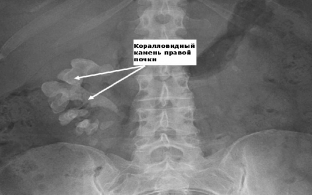

X-ray findings in urolithiasis

Important information in urolithiasis is provided by an X-ray examination, which should begin with a survey urography. On the X-ray image, the shadows of the formed stones are visualized, which makes it possible to clarify the place of their localization. After the introduction of a contrast agent, excretory urography is performed, which allows obtaining information about the anatomical and functional changes in the kidneys. The degree of expansion of the renal structures, their characteristic changes are determined. Often the radiopaque substance fills the pyelocaliceal system of the kidneys to the level of their obstruction. In patients with complete patency, retrograde ureteropyelography is performed.